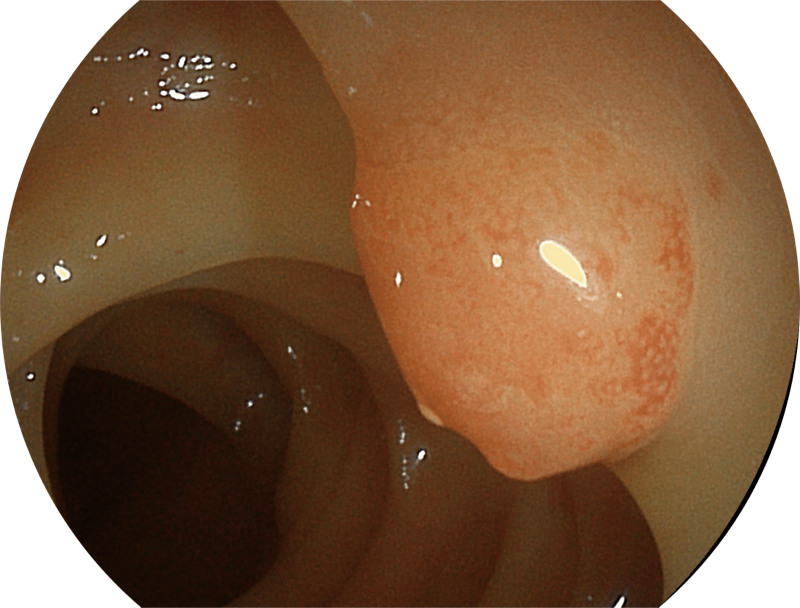

百万级像素高清传感器,1080P全高清视频信号输出,图像清晰。

能够凸显黏膜浅层和中层血管轮廓,适用于中、远景观察下的病灶识别和早癌筛查。

SFI图像

能够凸显黏膜浅层血管轮廓和黏膜表面微结构,适用于中、近景观察下的早癌精确诊断。